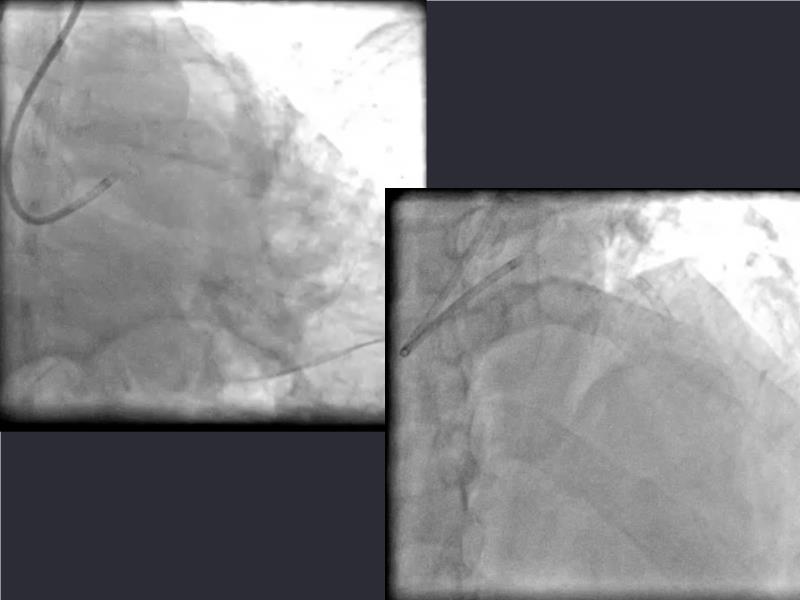

This session is a valuable resource for grasping innovative strategies in handling bifurcation and extended diffuse lesions through dedicated stenting solutions. Explore insights into the advanced Myval next-generation THV technology, unveiling its distinctive features, procedural advantages, and clinical outcomes across a diverse patient pool. Gain understanding into the CorAlign technique, ensuring accurate commissural and coronary alignment while maintaining coronary access. Additionally, delve into the techniques for precise sizing, positioning, and deploying of Myval THV.

- To understand novel tools and techniques for effective management of bifurcation lesions and long diffused lesions using dedicated stenting solutions